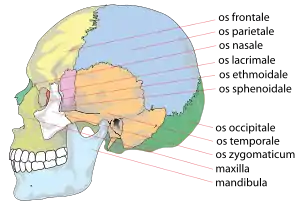

Kraniet set fra siden | |

Hjernekassen dannes af nedenstående seks knogler:

- Isseben (1 par, Latin: Os parietale)

- Kileben (Os sphenoidale)

- Nakkeben (Os occipitale)

- Pandeben (Os frontale)

- Siben (Os ethmoidale)

- Tindingeben (1 par, Os temporale)

Hjernekassen beskrives som regel ved at opdele denne i to dele kaldet theca cranii og basis cranii, hvor sidstnævnte beskrives som hhv. basis cranii interna og basis cranii externa. Theca cranii er den del af kraniet, der kan ses oppefra, basis cranii externa er den del af kraniet, der kan ses nedefra, når underkæben er fjernet, og basis cranii interna er den del af kraniet, der kan ses oppefra, når theca cranii er fjernet.